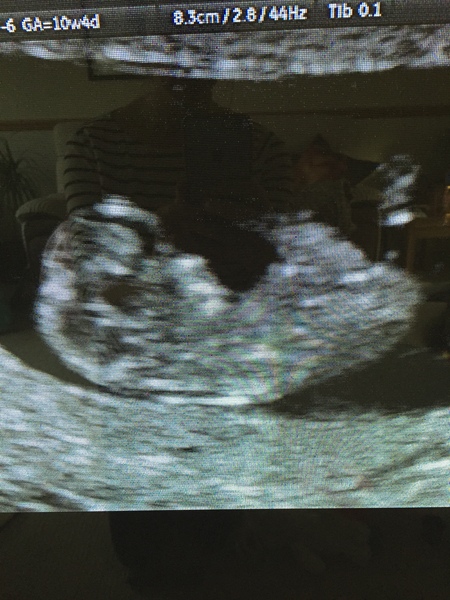

Fox, we ended up having a private scan a few weeks back. I thought the TWW was bad until we got pregnant and started waiting for the scan! I'd messed work about so much, I felt that I needed to tell them, but wanted to see that all was progressing as planned first... and on that note, great pic, Niks. They grow so much in the run up to the 12-week scan, don't they? Can't wait for ours next week!